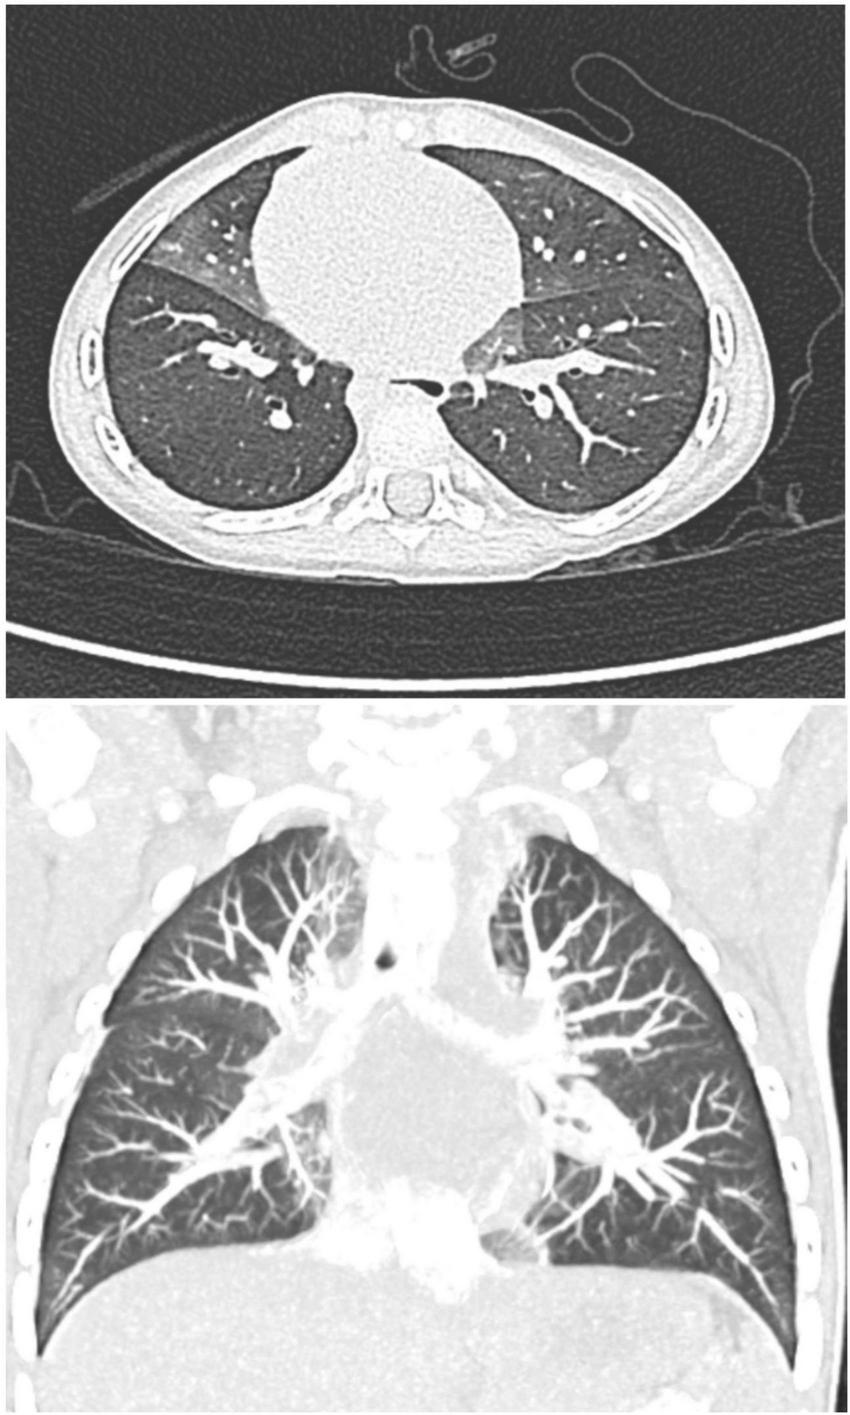

Lung biopsy demonstrating increased numbers of PNECs within bronchioles and alveolar ducts without evidence of other abnormalities has historically been the diagnostic gold standard for NEHI (16, 17). However, computerized tomography (CT) of the chest has been increasingly used as a non-invasive test to support clinical suspicion given its relatively high sensitivity and specificity (78 and 100%, respectively) (18, 19). Current guidelines from the American Thoracic Society recommend the use of CT scanning without lung biopsy for diagnosis of chILD except in patients with atypical clinical or CT findings (20). Characteristic CT findings include ground-glass opacification confined to the middle lobe, lingula, and paramediastinal regions of the lungs, in addition to mosaic areas of air-trapping (4, 19).

He first presented to the pediatrician’s office at 6 months of age for 2 weeks of dry cough and hypoxemia. The parents had recently bought a consumer-grade pulse oximetry-based home baby monitoring device and noticed low oxygen saturations (SpO2: 83–91%) on the device at night. Exam was notable for tachypnea, subcostal retractions, decreased breath sounds, mild scattered wheezes, and bilateral crackles. No fevers were reported. He was diagnosed with bronchiolitis and superimposed pneumonia and was prescribed antibiotics. Within a few weeks of initial presentation, he was hospitalized twice for persistent symptoms of tachypnea and hypoxemia (both during the day and night) with presumed diagnoses of recurrent bronchiolitis and reactive airway disease. He was treated with supplemental oxygen, albuterol, and oral and inhaled steroids. Chest x-ray (CXR) showed a patchy opacity in the right mid-lung field. Respiratory viral panels were negative. Echocardiogram was normal. He continued to have persistent tachypnea, retractions, and crackles on exam outside of acute respiratory illnesses, and his parents continued to report hypoxemia at night on their home monitor. These concerns along with his poor weight gain prompted formal polysomnography. The sleep study showed obstructive sleep apnea (Apnea Hypopnea Index of 5.5) and episodes of persistent hypoxemia below SpO2 90%, and he was referred to a pediatric pulmonologist. Repeat CXR showed patchy ill-defined perihilar opacities. Sweat chloride test was normal and immune work-up was unrevealing. A bronchoscopy with bronchoalveolar lavage was normal. He ultimately underwent a high-resolution CT scan which showed areas of mosaic attenuation and geographic ground-glass opacities in a predominant perihilar distribution, supporting the diagnosis of NEHI (Figure 2).

Figure 2. Axial and coronal high-resolution CT chest, demonstrating characteristic geographic ground-glass opacities centrally and most prominently in the right middle lobe and lingula, highly consistent with NEHI.